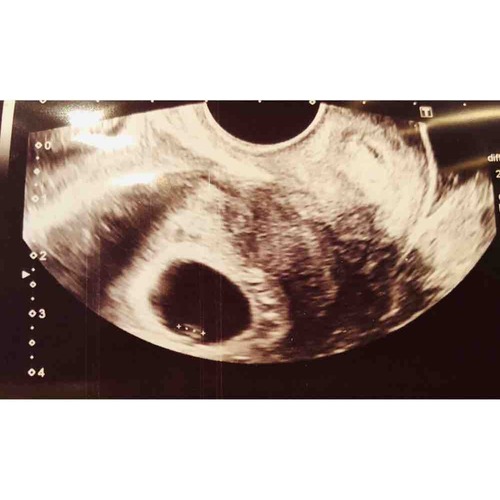

Het was gelukkig goed! Ik zat er echt helemaal klaar voor slecht nieuws maar niets was minder waar! We zagen het direct! Klein maar fijn en er knipperde zelfs al iets! 💕 Vrijdag terug en dan 1x per week op controle 🥰